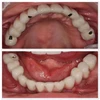

زراعة الفم والأسنان